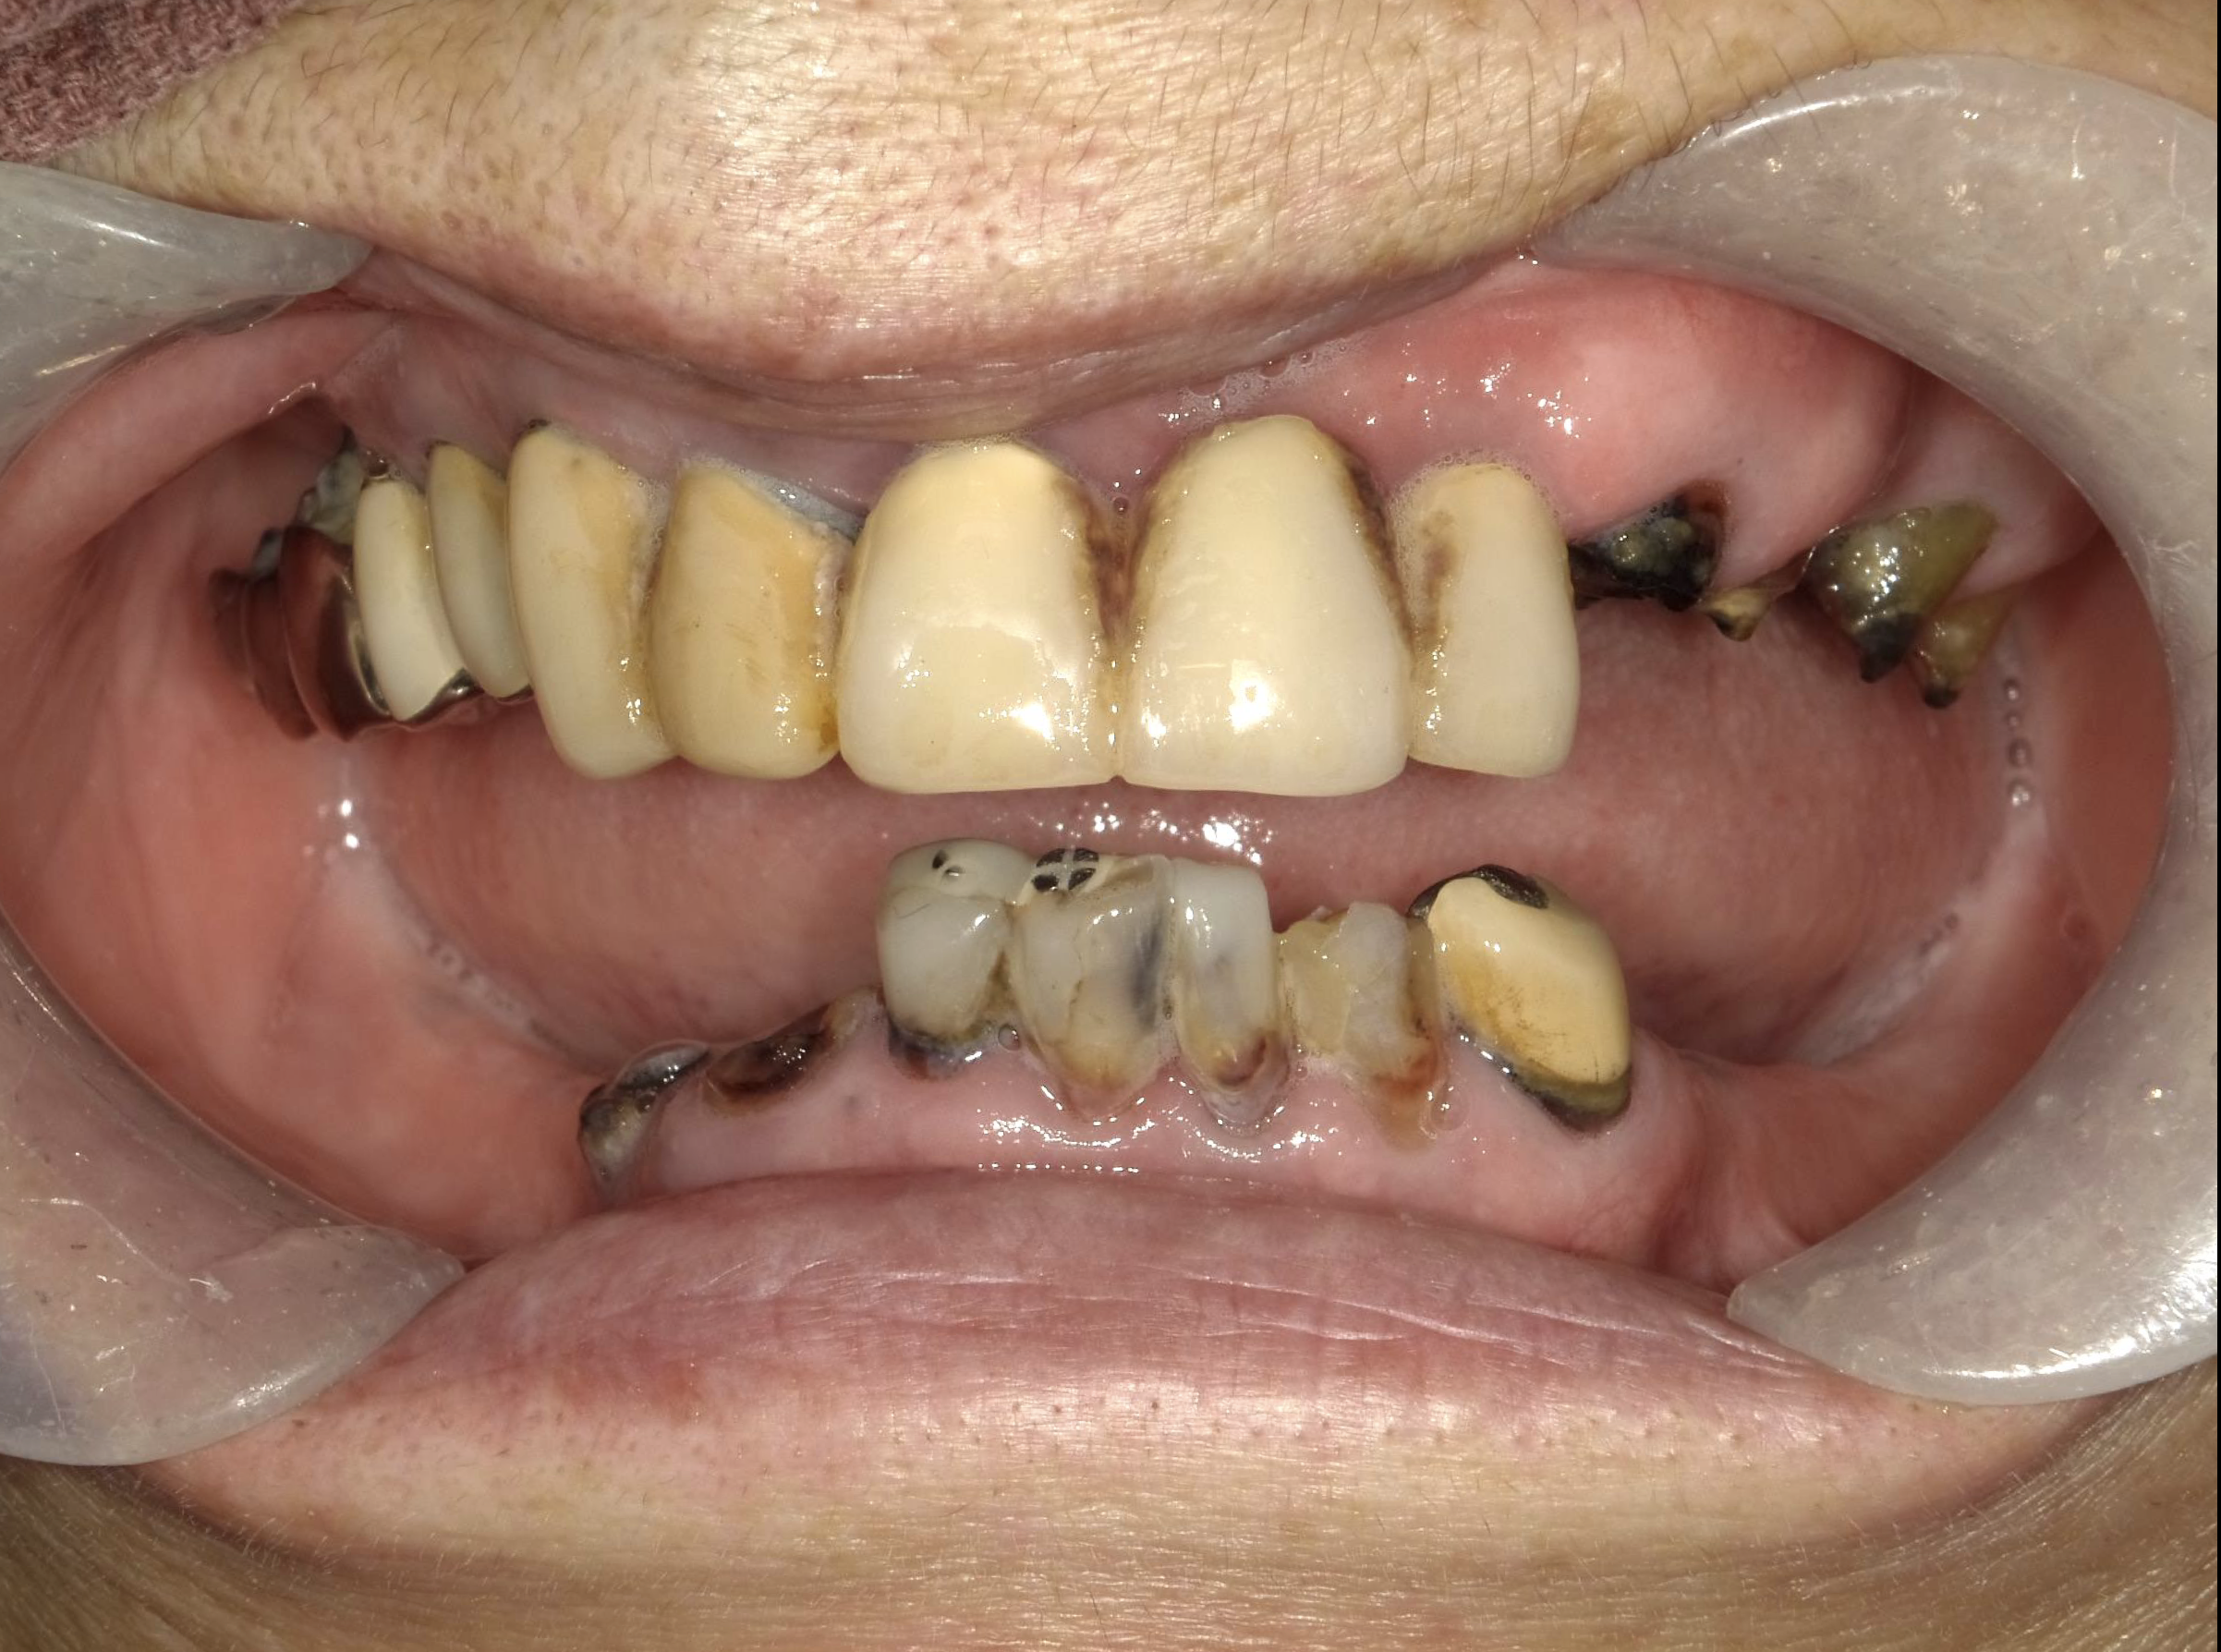

歯がボロボロですが見てもらえますか?

-

A

当院では長年の放置により口腔内がボロボロになってしまった方など様々なお悩みをお持ちの方でも対応可能です。その人にあった治療方法をご提案させていただきます。

ボロボロの口腔内から改善をされた方の症例がございますので症例集をご覧ください。